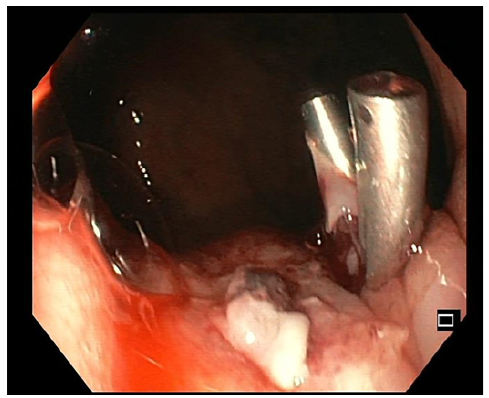

We present the case of an asymptomatic 26-year-old male, non-smoker, overweight, with no prior family history of cancer who presented to the emergency department (ED) due to a 2-day history of melena and asthenia. Although the patient appeared pale, his hemodynamic condition was stable. Anemia was evident from his blood count, revealing a hemoglobin of 7.1 g/dL. An emergency upper endoscopy showed a Forrest Ib ulcer situated at the cardia, displaying active oozing (shown in Fig. 1). An injection of 3.5 mL of diluted adrenaline (1:10,000) and an additional 3.5 mL of polidocanol 2% effectively managed the condition. The clinical presentation was assumed to be a possible Mallory-Weiss syn-drome, and the patient was discharged after a 5-day observation period. As it was an ulcer at the cardia, a follow-up endoscopy was scheduled in 12 weeks.

Fig. 1 Forrest Ib ulcer with active oozing at the cardia treated with diluted adrenaline and polidocanol injection since clip placement in the vessel was unsuccessful.